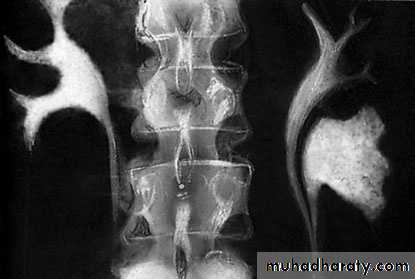

U/S: hydronephrosisIVU: diagnostic , hydronephrosis with fixed stenotic segment or complete obstruction

CT scan: hydronephrosis that ends abruptly

Open & laparoscopic surgical techniques Anderson-Hynes dismembered pyeloplasty: excision of the pathologic UPJ & appropriate reanastamosis or flap technique or flap operation

PUJ Obstruction – gross pathology